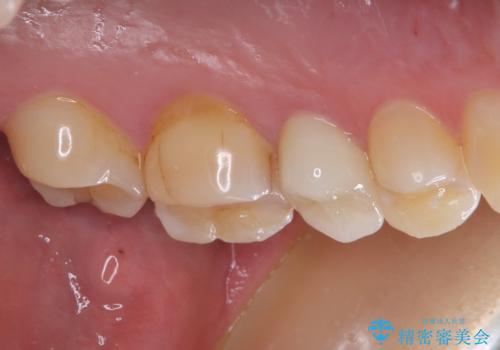

根管治療を行った奥歯は、再発防止や残された歯質を守るため、クラウンによる補綴治療が必要となります。

補綴後数ヶ月経過しレントゲンを撮影したところ、根尖周辺の病変が消退してきていることが確認できました。